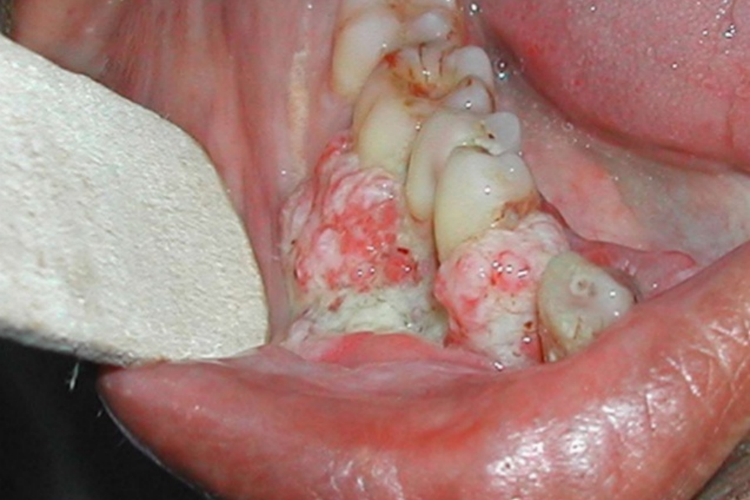

牙龈癌:起始多源于牙间乳头及龈缘区。溃疡呈表浅、淡红,以后可出现增生。由于黏骨膜与牙槽突附着甚紧,较易早期侵犯牙槽突骨膜及骨质,进而出现牙松动,并可发生脱落。X线片可出现恶性肿瘤的破坏特征——虫蚀状不规则吸收。